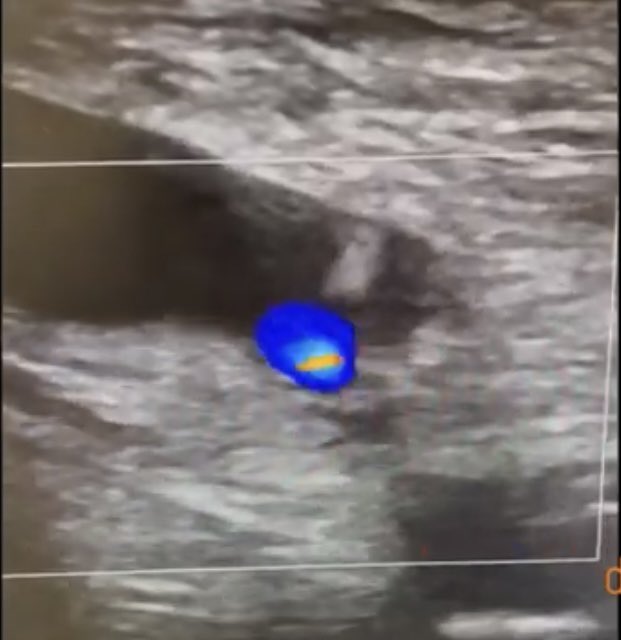

7/ #CathLabHack Go sheathless with the IVUS from the other side for imaging and also venography through the IVUS To help land the stent #DVT #MayThurner #VTE #Cardiotwitter #IRAD #VascTwitter

Go sheathless with the IVUS from the other side for imaging and also venography through the IVUS To help land the stent

#DVT #MayThurner #VTE #Cardiotwitter #IRAD #VascTwitter